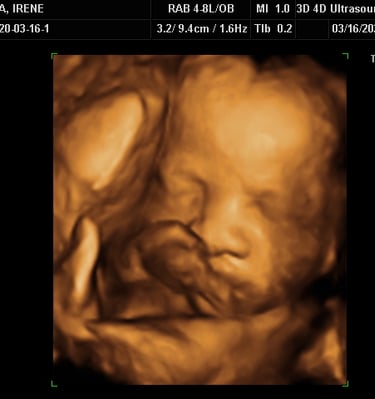

Our Gallery

Explore beautiful moments captured during our 3D and 4D sessions.